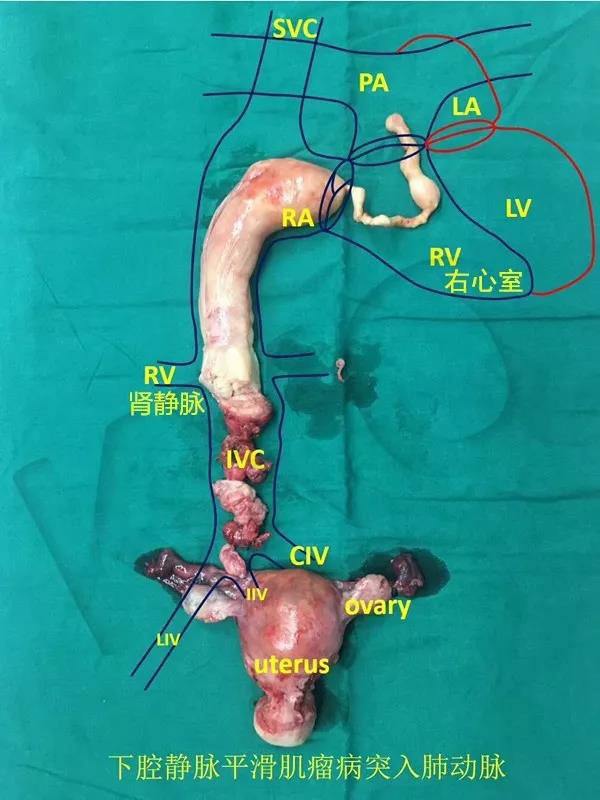

近期,山东省立医院接诊了一名特殊的患者,经腹部强化CT检查显示,患者患有子宫血管平滑肌瘤,而瘤子沿着血管从子宫一直长到心脏!山东省立医院心外科、妇科、血管外科、肝胆外科、麻醉科、输血科等多科室联手,共同为患者实施手术,成功摘除了这个自右侧髂内静脉到主肺动脉的长近半米的肿瘤。

该患者今年50岁,半年前开始出现活动后胸闷憋喘症状。近期因症状明显加重,同时伴有腹胀、纳差等症状,遂来我院就诊。经腹部强化CT检查后发现,患者的子宫血管平滑肌瘤沿着右侧髂内静脉、右髂总静脉、下腔静脉一路生长,直达右心房!心脏超声显示,瘤子在患者右心房形成5厘米×3厘米大小的瘤栓,又向右心室延伸成长约7.15厘米的不规则长条形,并继续向肺动脉瓣口延伸。

在游离下腔静脉的过程中,患者突发室颤,血压迅速降低,病情危急,心脏大血管外科主任医师王正军、主治医师朱小龙果断进行电除颤及胸内心脏按压,同时建立体外循环,主治医师张军开启体外循环机,确保手术继续安全进行。患者的生命体征很快恢复平稳并进入手术最后阶段。由心脏大血管外科专家团队切开患者右心房,与血管外科专家团队共同努力,完整剥离出了自右侧髂内静脉到主肺动脉的长达近半米的肿瘤(如图所示)。